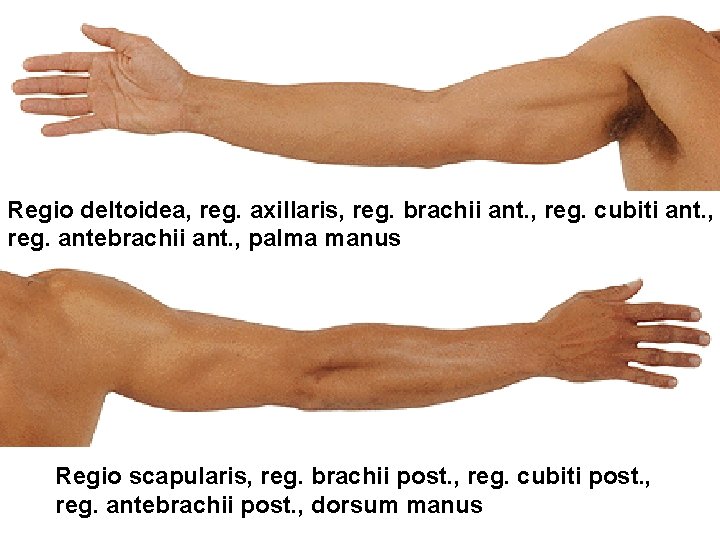

Regio deltoidea, reg. axillaris, reg. brachii ant. , reg. cubiti ant. , reg. antebrachii ant. , palma manus Regio scapularis, reg. brachii post. , reg. cubiti post. , reg. antebrachii post. , dorsum manus